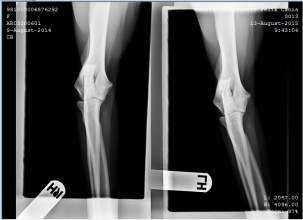

Keith 2 Published August 14, 2015 at 703 × 511 in Hip and Elbow X-ray’s Keith and Alexa ← Previous Next → Keith